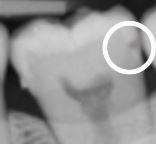

Developmental staging of carious lesions is pivotal for appropriate ethical clinical decision-making in contemporary caries management. Accurate assessment of lesion extent/severity (staging) and activity (grading) allows practitioners to provide the most appropriate preventive advice and suitable interventions, enabling the implementation of evidence-based, person-focused, prevention-based, team-delivered and susceptibility-related phased minimum intervention oral care. Minimally invasive dentistry remains an important operative interventive option for cavitated lesions, but intervening at the right stage ensures patients are not started on an irreversible, destructive restorative cycle unnecessarily. This article provides an update on recommended practical methods for staging the extent/severity and grading the activity of dental carious lesions, especially for those clinical teams delivering primary care and needing to navigate remuneration systems.

龋病损的发展阶段对于当代龋病管理中适当的伦理临床决策至关重要。准确评估病变范围/严重程度(分期)和活动度(分级)可使从业者提供最合适的预防建议和适当的干预措施,从而实施基于证据、以患者为中心、基于预防、团队提供和易感性相关的分阶段最小干预口腔护理。微创牙科仍然是对龋洞性病变的重要手术干预选择,但在正确的阶段进行干预可确保患者不会不必要地开始不可逆、破坏性的修复循环。本文提供了一种更新的方法,用于分期评估龋病损的范围/严重程度和分级病变活动度,特别是对于那些提供初级保健且需要导航薪酬系统的临床团队。